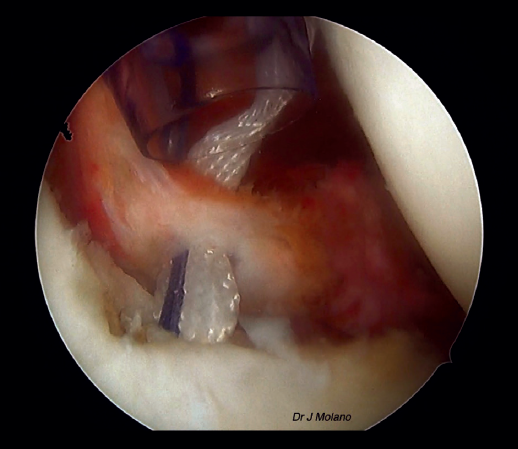

Tras ello, se cambia nuevamente la visión al portal posterior y se empieza con la preparación glenoidea de la ligamentoplastia de hombro. Se coloca con motor una aguja de Kirschner de 2,2 mm de diámetro a las 3 horas (hombro derecho) o 9 horas (hombro izquierdo), utilizando como guía la de PushLock® (Arthrex, Naples, FL, USA). Sobre ella se realiza un túnel de 4,5 × 20 mm con broca canulada de 4,5 mm. Posteriormente, se fija el ligamento AchilloCord PLUS® (Xiros, Leeds, UK) en la cara anterior de la glena mediante un tornillo interferencial de tenodesis de tipo Peek® de 4,75 × 15 mm (Arthrex, Naples, FL, USA). Se mantiene en el portal anterior, pero por fuera de la cánula, el ligamento y se continúa con la reparación de Bankart. Habitualmente, en nuestro centro se realiza con 2 anclajes de tipo Iconix® de 1,4 mm, de tipo todo hilo, por debajo de la implantación del ligamento y 1 o 2 por encima que pueden ser Iconix® o PushLock®.

Figura 6. Visión artroscópica desde el portal posterior de la ligamentoplastia en hombro derecho previa a la reparación capsulolabral.